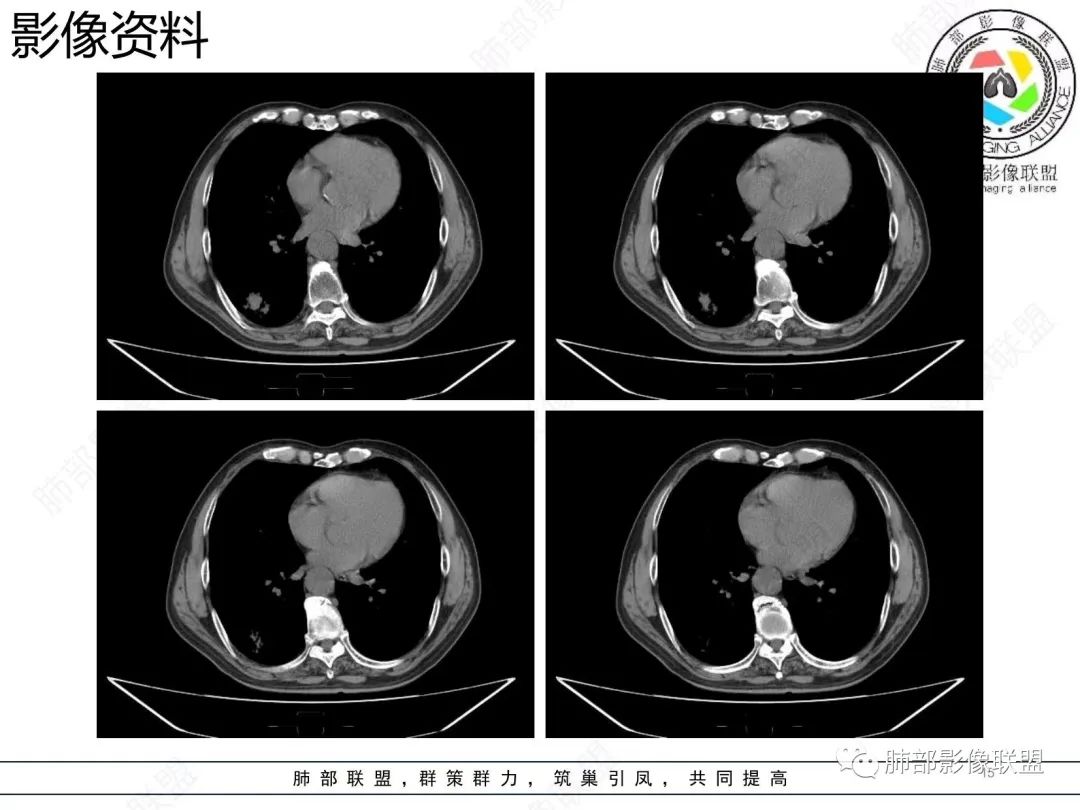

老年男性 右肺下叶胸膜下见一团状实性病灶+边缘磨玻璃,边缘形态不规则,,局部有平直,长轴平行于胸膜面,整体收缩力偏弱,邻近胸膜面轻度增厚,纵隔窗显示病灶内可见支气管充气,考虑炎性肉芽肿,隐球菌可能,鉴别黏液腺癌。

结节型粘液腺癌,具有血管弯,支气管截断,磨玻璃边界清楚等恶性征象,同时磨玻璃内部较糊,似清非清,不符合普通腺癌附壁生长特点,更像局限的粘液成分。收缩力不强,胸膜局部微积液,内部小空洞(考虑局部粘液排除形成),所以考虑结节型粘液腺癌。

区别1:结节期(影像说结节型)粘液腺癌,粘液成分还大多数局限于粘液腺癌细胞的胞浆中,没有飘出去,所以粘液密度不明显,周围的磨玻璃成分大多数还是分散于肺泡壁上的粘液腺癌细胞,所以边界相对较清楚(时间越晚,飘出去的粘液越多,边界就会越不清楚了),因为胞浆中的粘液成分显得较糊,有点似清非清。而普通腺癌附壁生长的腺癌细胞胞浆中没有粘液,所以非常清楚。

区别2:粘液腺癌的MGGN收缩力不强,普通腺癌的MGGN收缩力明显。

1.结节型肺粘液腺癌以中老年女性多见,单发,发病部位常位于两下肺胸膜下(肺外周带)。

2.多数病灶具备典型恶性肿瘤征象,但是不典型者仍不少见。可有分叶和棘状突起,但较少出现典型毛刺征。强化程度不如一般的腺癌病灶那么显著。

3.病灶常呈圆形或不规则形,实性结节略多于混合磨玻璃结节,少见于纯磨玻璃结节;或囊实性结节影或肿块,密度混杂,部分可出现钙化;病灶边界可清楚,也可模糊,须与炎性结节鉴别;周围可有类圆形磨玻璃密度卫星灶;表现为实性结节病灶,收缩力可能表现不明显,较少胸膜凹陷或血管集聚,须与良性结节鉴别。

4.原发性肺粘液腺癌侵袭力相对较低,发展慢;病灶较少破坏支气管及血管,可表现为血管造影征及空气支气管征。较少胸膜侵犯,也较少肺门纵隔淋巴结转移。

3.粘液的重力效应致使病灶常位于胸膜下或叶间胸膜附近。

5.粘液的张力(占位效应)常可抵消病灶收缩力,致使病灶收缩力表现常较弱。